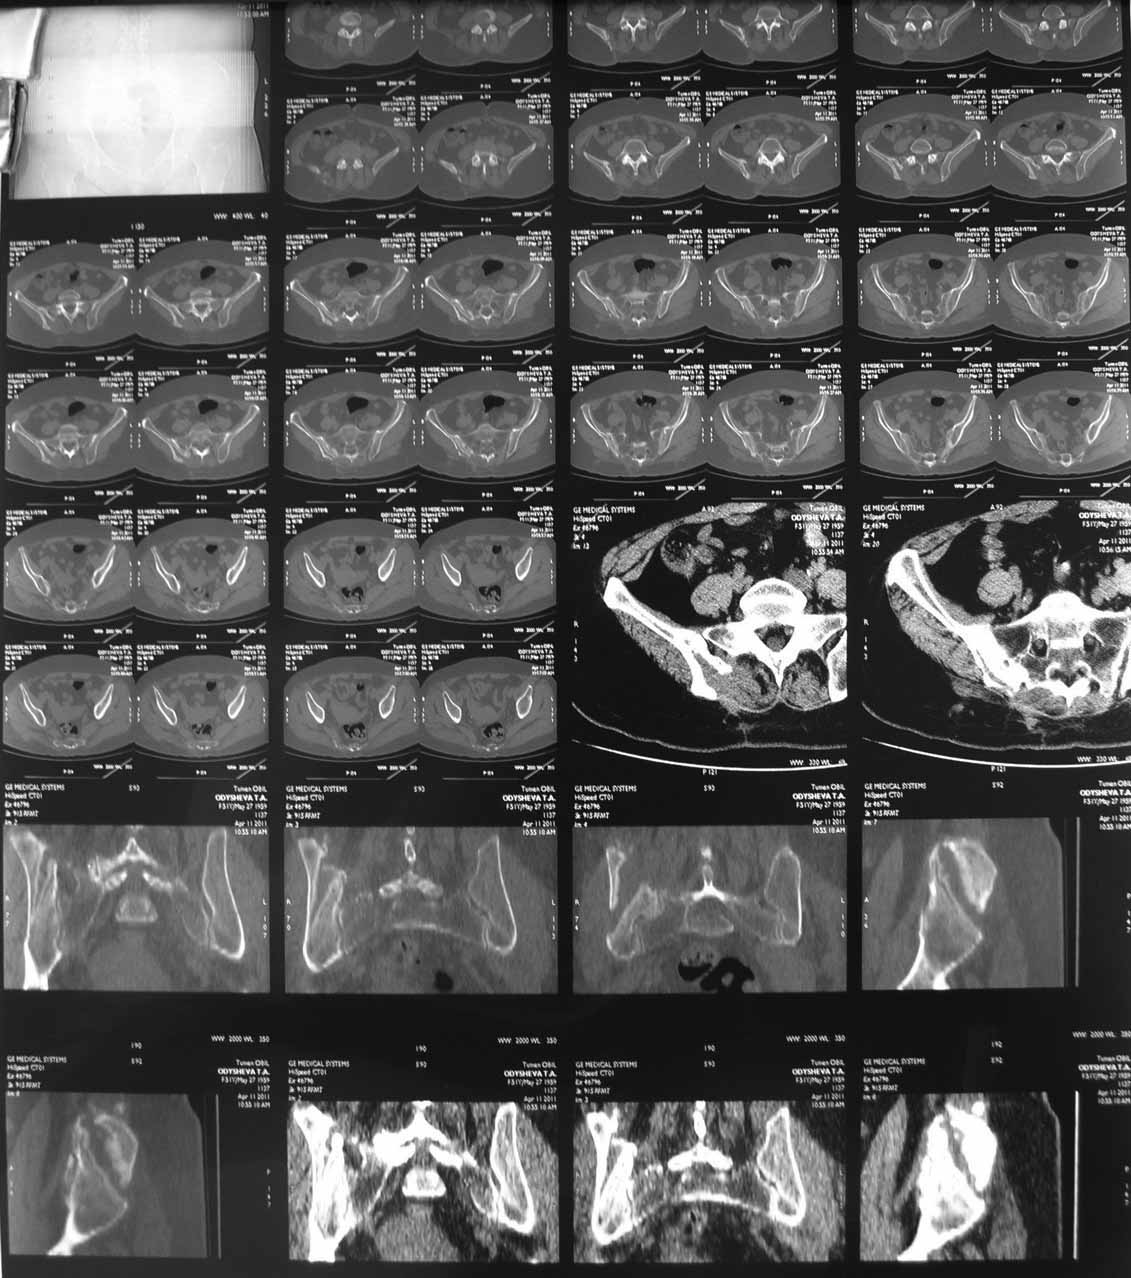

В 2009г установлен диагноз - сакроилеит справа.На представленных КТ имеется гипертрофия заднего отдела правой подвздошной кости с образованием контакта с задней поверхностью крестца.В январе 2011 года выполнена попытка удаления гипертрофированного участка подвздошной кости. удаленные участки кости исследованы гистологически - губчатая кость с элементами гиалинового хряща. После операции положительного эффекта не получено. На контрольной КТ от 04.2011 обнаружено что, желаемого результата операции не получено(интересующий участок удален частично), при этом имеется расслоение заднего отдела правой подвздошной кости.

На первичных КТ от 19-12-2009 определяется частичное анкилозирование правого крестцово-подвздошного сочленения, а на последних, от 11-04-2011 протяженность анкилозированной зоны значительно больше - сакроилеит прогрессирует, (с левой стороны вроде тоже признаки сакроилеита появились - не очень понятно из-за качества снимка). Значимых дуральных и радикулярных конфликтов действительно нет. "расслоение кости" - рентгенологически выглядит как травматический перелом подвздошной кости. Что делать? - наверное, искать серонегативные спондилоартропатии у ревматолога.